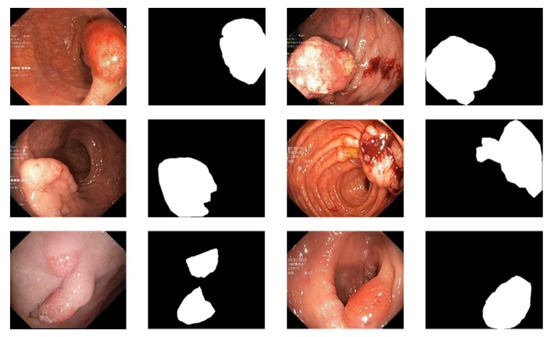

Figure 5 is a comparison of the direct prediction map of the model and the conditional random field after refining the boundary. A conditional random field can effectively fine-tune the boundary of a segmented image. In our work, a high-density conditional random field was applied to the experiment.

Figure 5.

The first column is the original input image, the second column is the mask map, the third column is the direct prediction map of the model, and the fourth column is the prediction map with the conditional random field added.